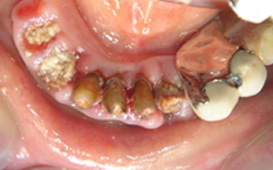

拆下牙橋後